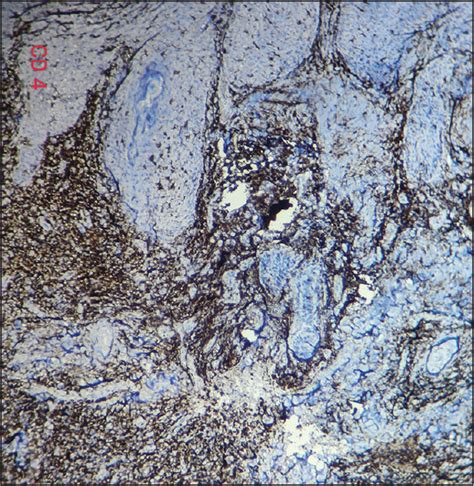

Okay, so you’re probably wondering, “How do I even know if I have this pseudolymphoma thing?” That’s a great question, guys, and it ties directly into why this condition can be so tricky to diagnose. The symptoms of pseudolymphoma can vary wildly depending on where it occurs in the body. Because it often mimics lymphoma, the symptoms can overlap significantly with cancerous conditions, which is why a thorough diagnostic workup is absolutely essential. The most common presentation is a palpable mass or lump . This could be in the skin, under the skin (subcutaneous tissue), in a lymph node (like in the neck, armpit, or groin), or even deeper within the abdomen or chest. If it’s in the skin, you might notice a raised, firm bump that can sometimes be tender or itchy. If it affects the lymph nodes, they might become enlarged and firm, which is often the first sign that makes people seek medical attention. People might think, “Oh, my glands are up,” and it could be an infection, or it could be this pseudolymphoma, or it could be actual lymphoma. That’s the diagnostic dilemma! When it occurs in the gastrointestinal tract, symptoms can be more varied and might include abdominal pain, nausea, vomiting, or changes in bowel habits. Sometimes, especially if it’s a larger mass, it might cause pressure symptoms on nearby organs. Often, pseudolymphoma is discovered incidentally . This means it’s found when a person is undergoing imaging or tests for an unrelated reason. For instance, a routine chest X-ray or CT scan might reveal an enlarged lymph node or a mass that wasn’t causing any noticeable symptoms. This highlights the importance of regular medical check-ups, even when you feel perfectly fine. The diagnostic process usually starts with a detailed medical history and physical examination . Your doctor will ask about your symptoms, any recent illnesses, medications you’re taking, and your general health. They’ll then carefully examine the affected area, feeling for lumps and checking for any other relevant signs. Imaging studies play a big role. This can include X-rays, ultrasounds, CT scans, or MRIs. These help visualize the size, shape, and location of the mass and can provide clues about its nature, but they rarely give a definitive answer on their own. The gold standard for diagnosing pseudolymphoma is a biopsy . This is where a sample of the abnormal tissue is removed and examined under a microscope by a pathologist. It’s a critical step because it allows the pathologist to analyze the cells’ appearance, arrangement, and specific markers. They are looking for features that indicate a reactive, benign process rather than a malignant, cancerous one. Sometimes, a small needle biopsy might be sufficient, while other times, a larger surgical biopsy might be needed to get an adequate sample. Special stains and immunohistochemistry are often used during the microscopic examination. These techniques use antibodies to identify specific proteins on the cells, which can help differentiate between different types of cells and determine if they are behaving abnormally. It’s like fingerprinting the cells to see who they are and what they’re doing. Because pseudolymphoma can mimic so many other conditions, including infections, benign tumors, and indeed, lymphomas, the diagnostic process can sometimes be lengthy and may require multiple tests and consultations with specialists. The key is that the diagnosis is confirmed by histopathology – the microscopic examination of tissue. So, while the symptoms might be vague or mimic other conditions, the definitive answer usually comes from that biopsy. It’s all about meticulous detective work by the medical team to get to the bottom of it. Now, let’s talk about what happens after they figure out what it is.